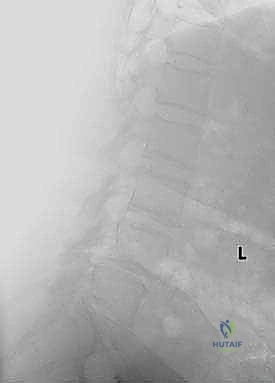

* الأشعة السينية (X-rays): خاصة الصور الديناميكية (أثناء الانحناء للأمام والخلف) لتقييم درجة عدم الاستقرار الميكانيكي والانزلاق.

* التصوير بالرنين المغناطيسي (MRI): المعيار الذهبي لتقييم الأنسجة الرخوة، ورؤية الأقراص الغضروفية، والأعصاب، والحبل الشوكي، وتحديد مكان الانضغاط بدقة متناهية.

* التصوير المقطعي المحوسب (CT Scan): يوفر صوراً ثلاثية الأبعاد للعظام، وهو ضروري جداً للتخطيط الجراحي الدقيق وتحديد أحجام المسامير المناسبة لكل سويقة فقارية.